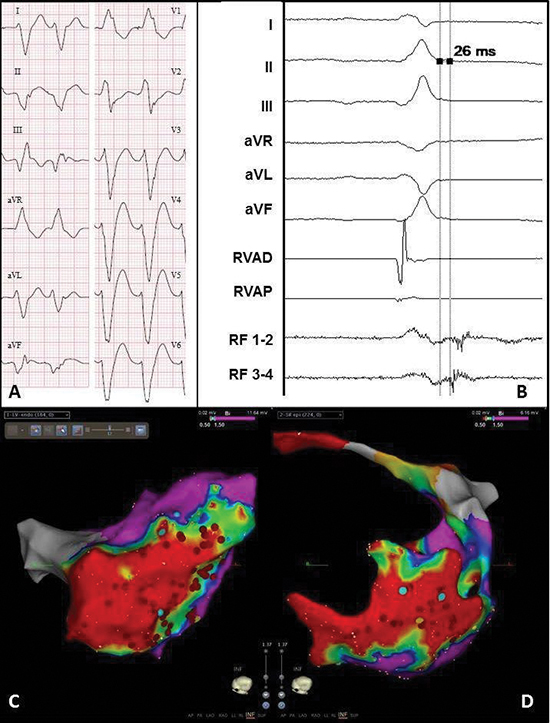

Figure 3 Electrocardiogram and electro-anatomical maps of case 1

A. Twelve-lead electrocardiogram showing a ventricular tachycardia (115bpm) with right bundle branch block morphology, right axis and early R-wave transition, suggesting a lateral mid-apical origin in the left ventricle. Pseudo delta wave and wide QRS suggest epicardial origin.

B. Recording obtained in sinus rhythm during the procedure showing local abnormal ventricular activation at the RF catheter. RVAD/P = right ventricular apex distal/proximal, RF = radiofrequency.

C. Inferior view of the bipolar endocardial voltage map showing a low voltage area from inferoposterior to low apical in the lateral wall (area 5/6/7). Red dots = RF applications.

D. Inferior view of the bipolar epicardial voltage map showing a low voltage area consistent with the endocardial

map. Red dots = RF applications.